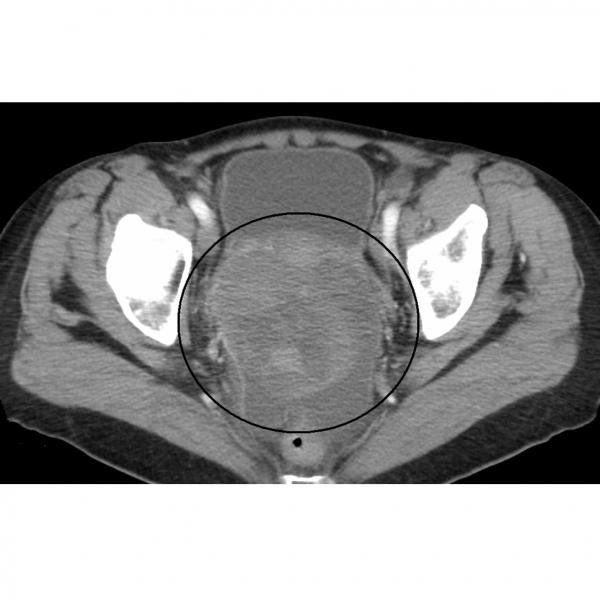

- CT scans

For information, visit CancerQuest's page on CT scans.